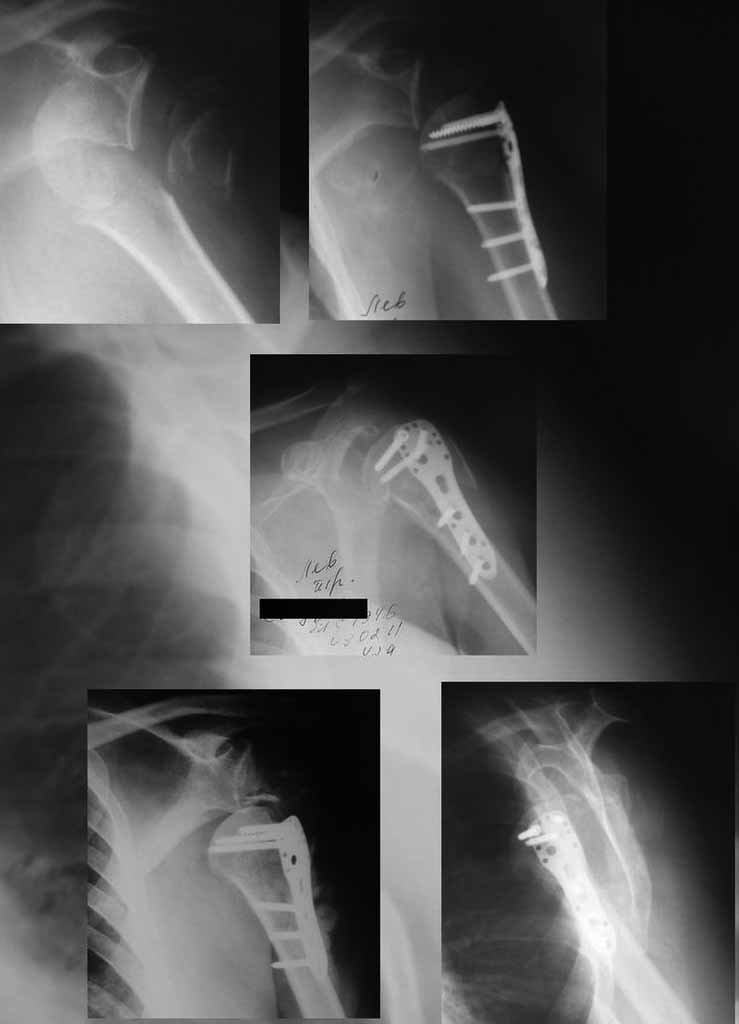

Вывих правого плеча после остеосинтеза пеерлома проксимального отдела плечевой кости пластиной |

Уважаемы коллеги! Прошу помочь определиться с тактикой лечения пациентки. В феврале в отделение поступила пациентка с оскольчатым переломо-вывихом головки плечевой кости. Выполнена операция -остеосинтез блокируемой пластиной. Костная пластика не производилась. На контрольных рентгенограммах остается сублюксация головки и смещение большого бугорка. Интраоперационно бугорок подшивался с помощью лавсановых нитей. Послеоперационно: ношение косыночной повязки и пассивные движения в плечевом суставе в течение 2,5-х месяцев без особенностей. Через 2,5 месяца при попытке выполнения пассивно-активных движений произошел передний вывих плечевой кости.Вся реабилитация производилась по месту жительства. Таким образом существование вывиха в течение 1 месяца. Боли не беспокоят. Нейрососудистых нарушений в конечности нет. Что вы можете посоветовать: пластику, эндопротез, артродез? Заранее спасибо.

мне кажется ,что на послеоперационном снимке, также имеется сублюксация головки.сколько годов пациентке?

Уважаемый коллега. На мой взгляд имеющаяся дислокация головки обусловлена на мой взгляд имеющейся у пациента обширной травмой ротаторного аппарата. В пользу данной точки зрения могу привести следующее: на представленных Вами рентгенограммах хорошо заметен отрыв большого бугорка со смещением отломков который как известно является точкой прикрепления коротких наружных ротаторов плеча. Последующая миграция данного фрагмента и неполноценная репозиция его при первичном остеосинтезе с нестабильной фиксацией на мой взгляд и обусловили создавшуюся ситуацию. то что пациента не беспокоят боли позволю подвергнуть сомнению поскольку сам занимаюсь хирургией плеча и с подобными ситуациями сталкивался неоднократно. На мой взгляд в настоящее время целесообразно проведение повторного оперативного вмешательства с адекватным восстановлением ротаторного аппарата, поскольку дальнейшее затягивание сложившейся ситуации уменьшает шанс на успех данного вмешательства.

Набор мелких снимков не отражает истинную картину суставной поверхности лопатки, а также качество репозиции головки плеча. Необходимо доказать аксиальным снимком наличие покрытия головки. Правильная маркировка на рентген снимках и соответствие с выставленным диагнозом гарантирует от ошибок со стороной во время операции!